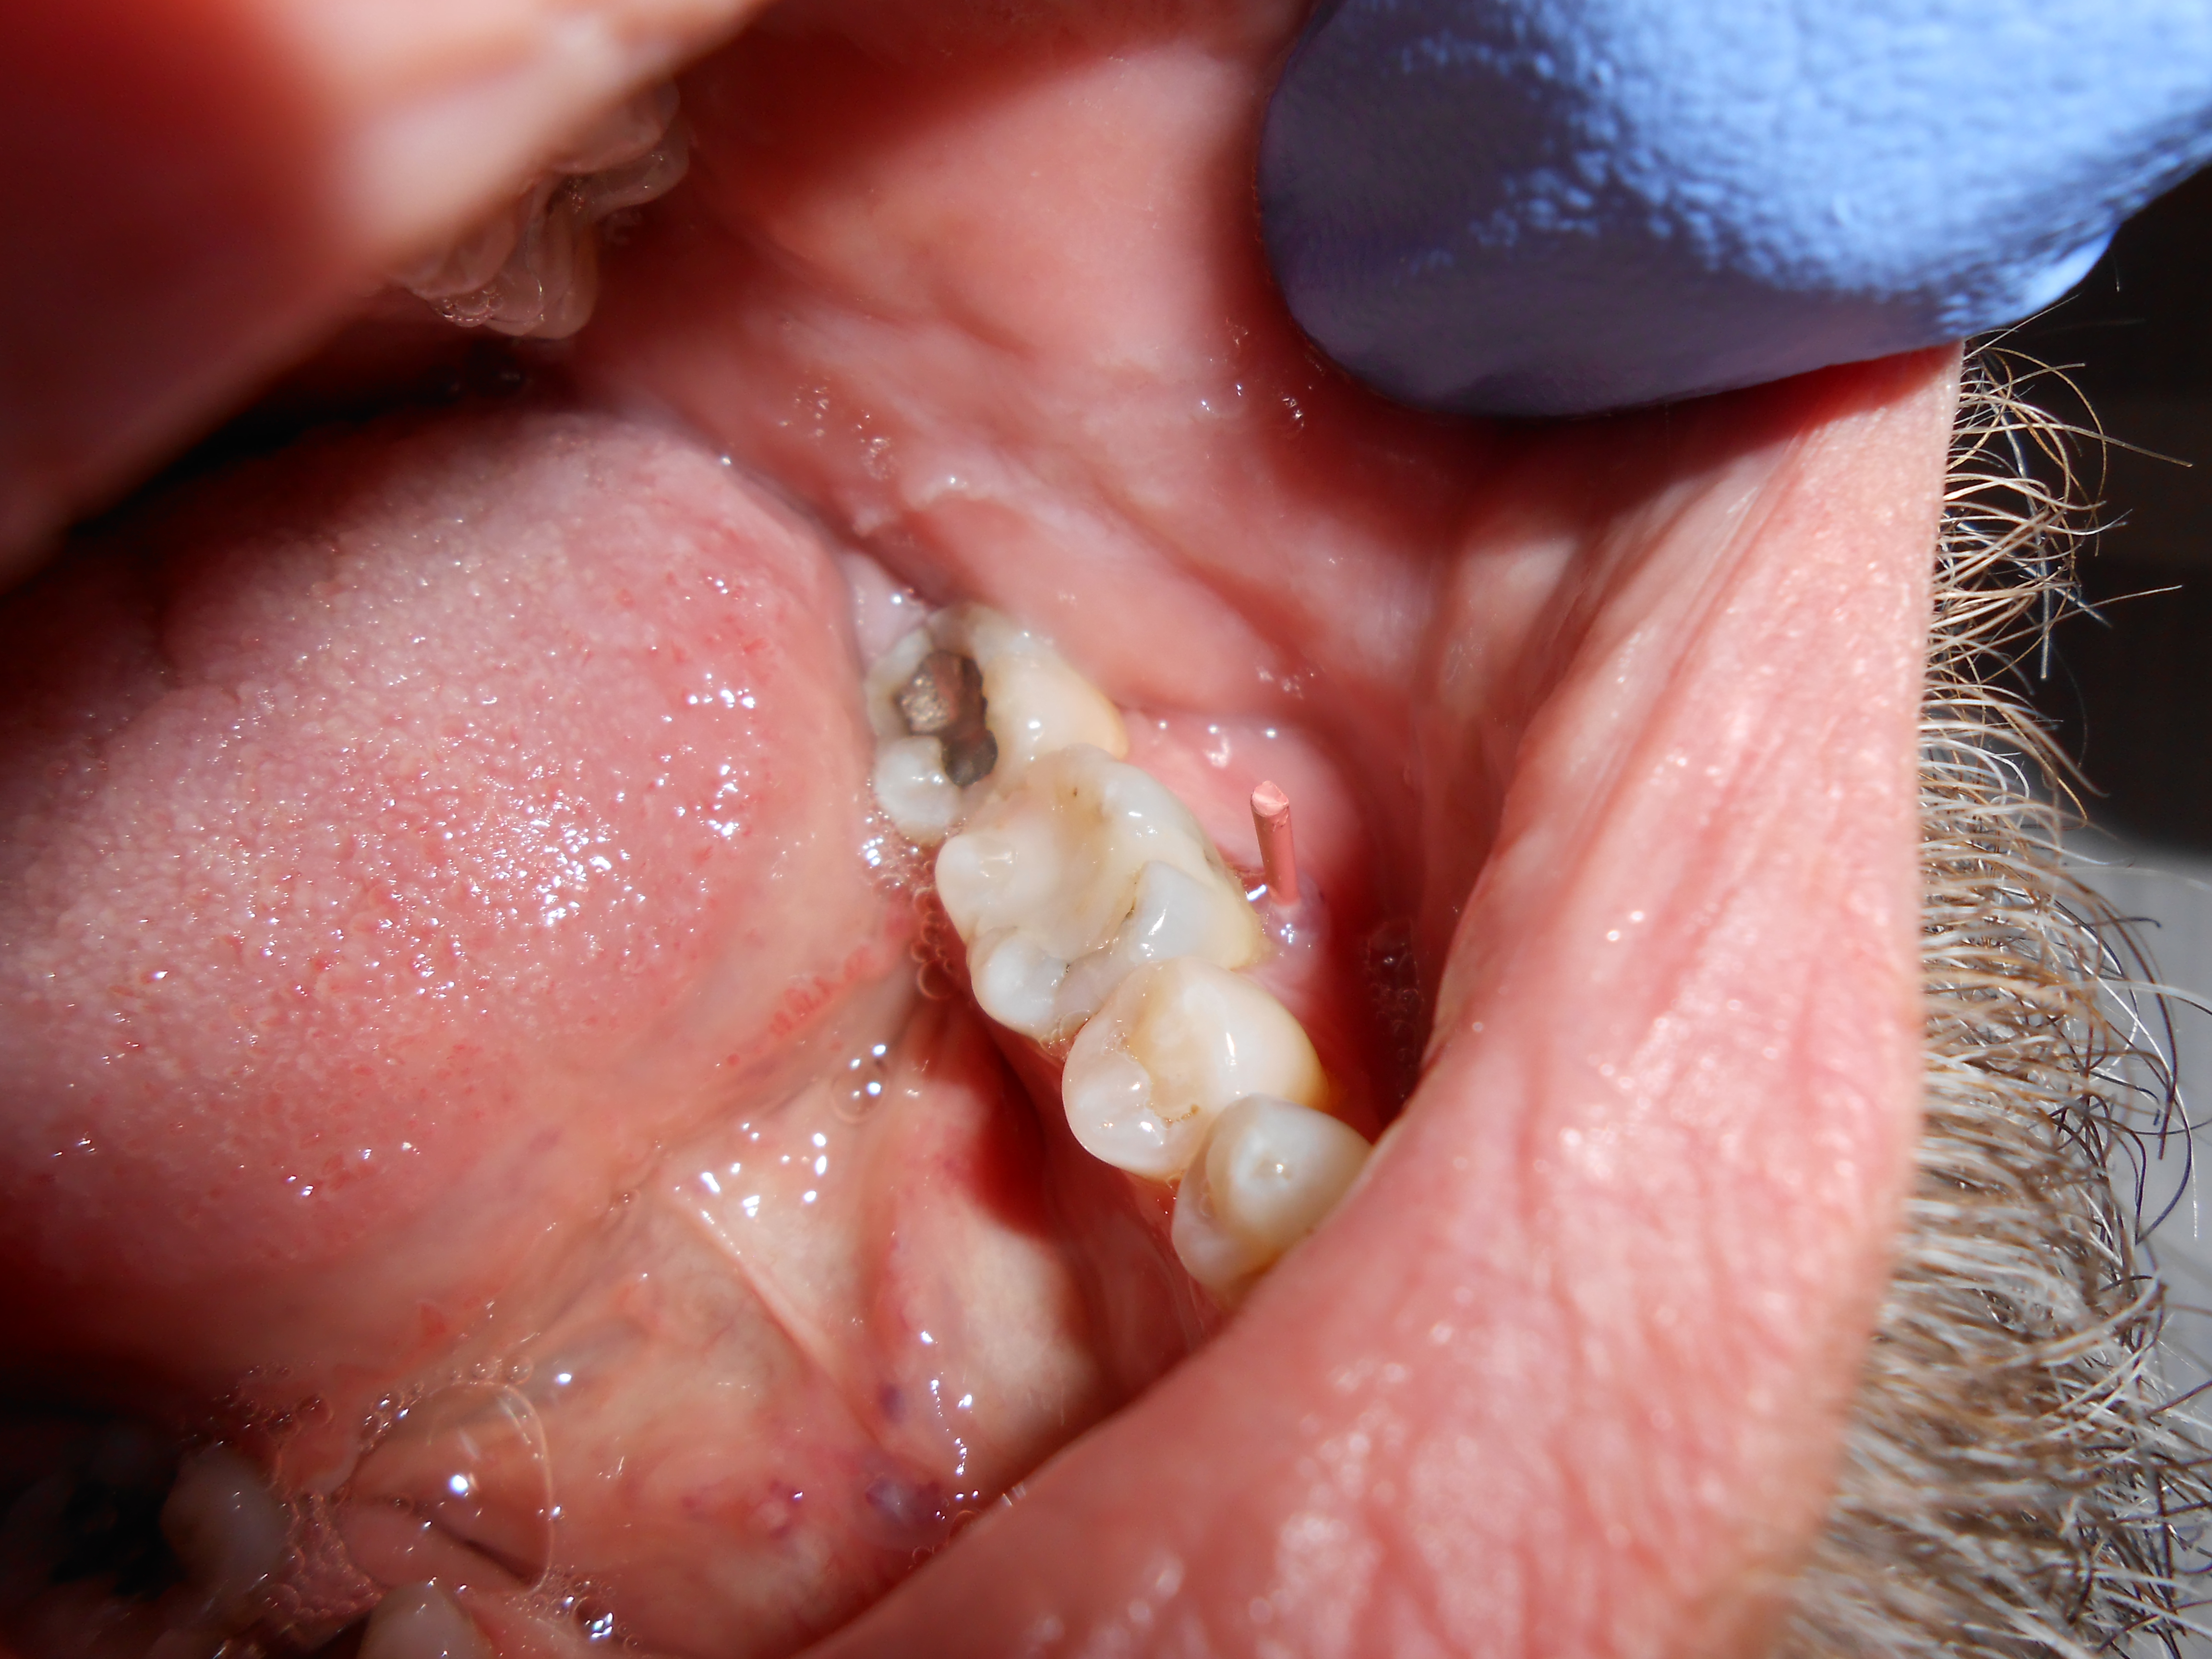

This test is often mistakenly considered to directly correlate to a pulp’s vitality. Although a tooth’s sensitivity to percussion tests may be due to a pulpitis or pulpal necrosis, it is only indirectly associated. All this specific test helps to determine is the status of the periodontal ligament (Figure 1). A bite test may also need to be performed if a patient complains about pain upon mastication.

Percussion testing on tooth No. 19 performed by tapping the buccal tooth surface with the opposite end of a dental mirror.

Figure 1